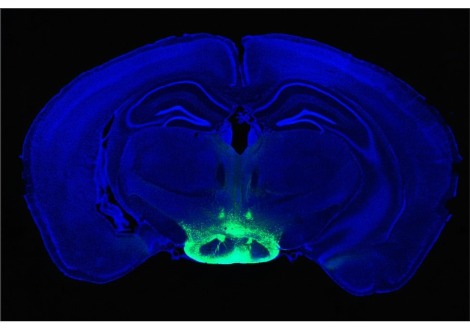

يظهر "تخطيط أمواج الدماغ" electroencephalogram نمط نوم الموجة البطيئة من النوم العميق لأحد المشاركين في الدراسة. قد تعزّز الاضطرابات في تلك المرحلة من النوم مرض الزهايمر.